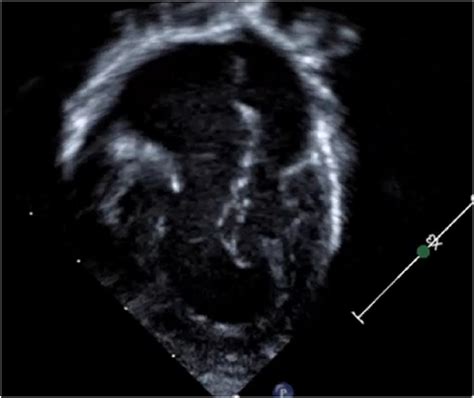

Modern advancements in pediatric cardiology have made early detection of Double Inlet Left Ventricle much more accurate. In many cases, the condition is identified during a prenatal fetal echocardiogram, allowing for a planned delivery at a specialized cardiac center. After birth, infants are monitored closely through a variety of diagnostic tools.

• double inlet lv echo